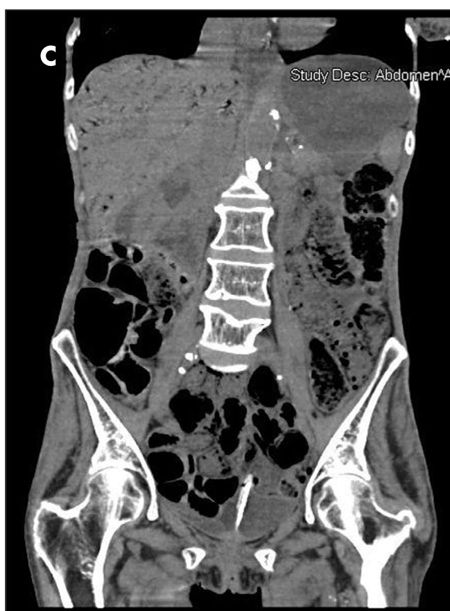

The patient complained of diffuse abdominal pain. She had an erythematous swelling around the right iliac fossa, abdominal guarding, and palpable crepitations. CT scan of the abdomen without contrast showed extensive portal venous air from the small branches in the periphery to the main portal and splenic veins (A and B). Considerable gaseous distention of the small bowel (C and D) and dilated loops of the small bowel were also seen (D and E). These findings were consistent with pneumatosis intestinalis.